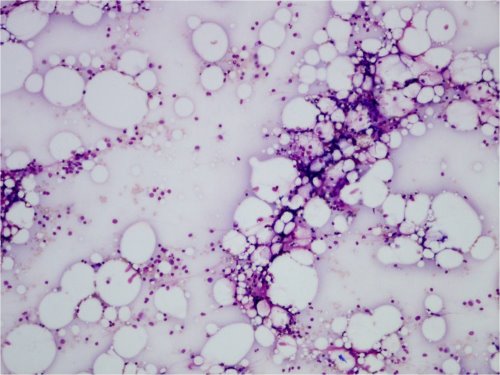

Aplastinen anemia

• Kohtalaisen harvinainen lapsilla

• Luuytimen kaikki linjat (erytropoieesi, myelopoieesi, trombopoieesi) ovat hypoplastisia tai aplastisia.

• Perifeerisessä veressä normosytäärinen anemia, leukopenia ja trombopenia

Kuva 1. Vaikea aplastinen anemia, yleiskuva. Näkyy rasvaa ja stroomaa, mutta ei juurikaan hematopoieesia.